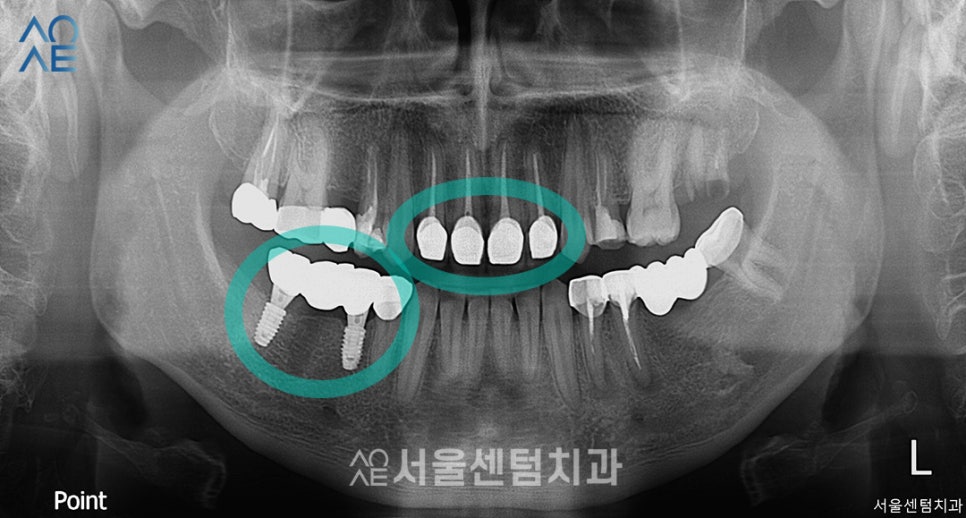

| (1) 현재 상태🔹 앞니 사이를 때우는 치료를 받았었음🔹 위, 아래에 깨진 치아 있음🔹임플란트가 필요한 부위에 브릿지 보철물 있음 |

| (2) 치료 계획🔹오른쪽 아래에 임플란트 2개 식립🔹앞니 지르코니아 4개 수복 |

20대 임플란트 식립

(사진상으로는 왼쪽)

오른쪽 아래 어금니를 총 3개 상실한 상태로

내원하셨던 환자분입니다.

기존 브릿지를 제거하고

2개의 임플란트만 식립해도

치아의 기능과 심미성을 모두 회복할거라

진단하였습니다.

다행히 뼈이식이 필요한 상태는 아니라서

별도 추가 진행은 하지 않습니다.